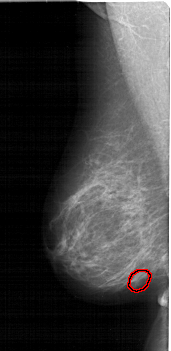

A_1915_1.LEFT_CC

LEFT_CC LINES 6346 PIXELS_PER_LINE 2941 BITS_PER_PIXEL 12 RESOLUTION 43.5 OVERLAY

FILE: A_1915_1.LEFT_CC.OVERLAY

TOTAL_ABNORMALITIES 1

ABNORMALITY 1

LESION_TYPE MASS SHAPE OVAL MARGINS OBSCURED

ASSESSMENT 3

SUBTLETY 2

PATHOLOGY BENIGN

TOTAL_OUTLINES 1

BOUNDARY